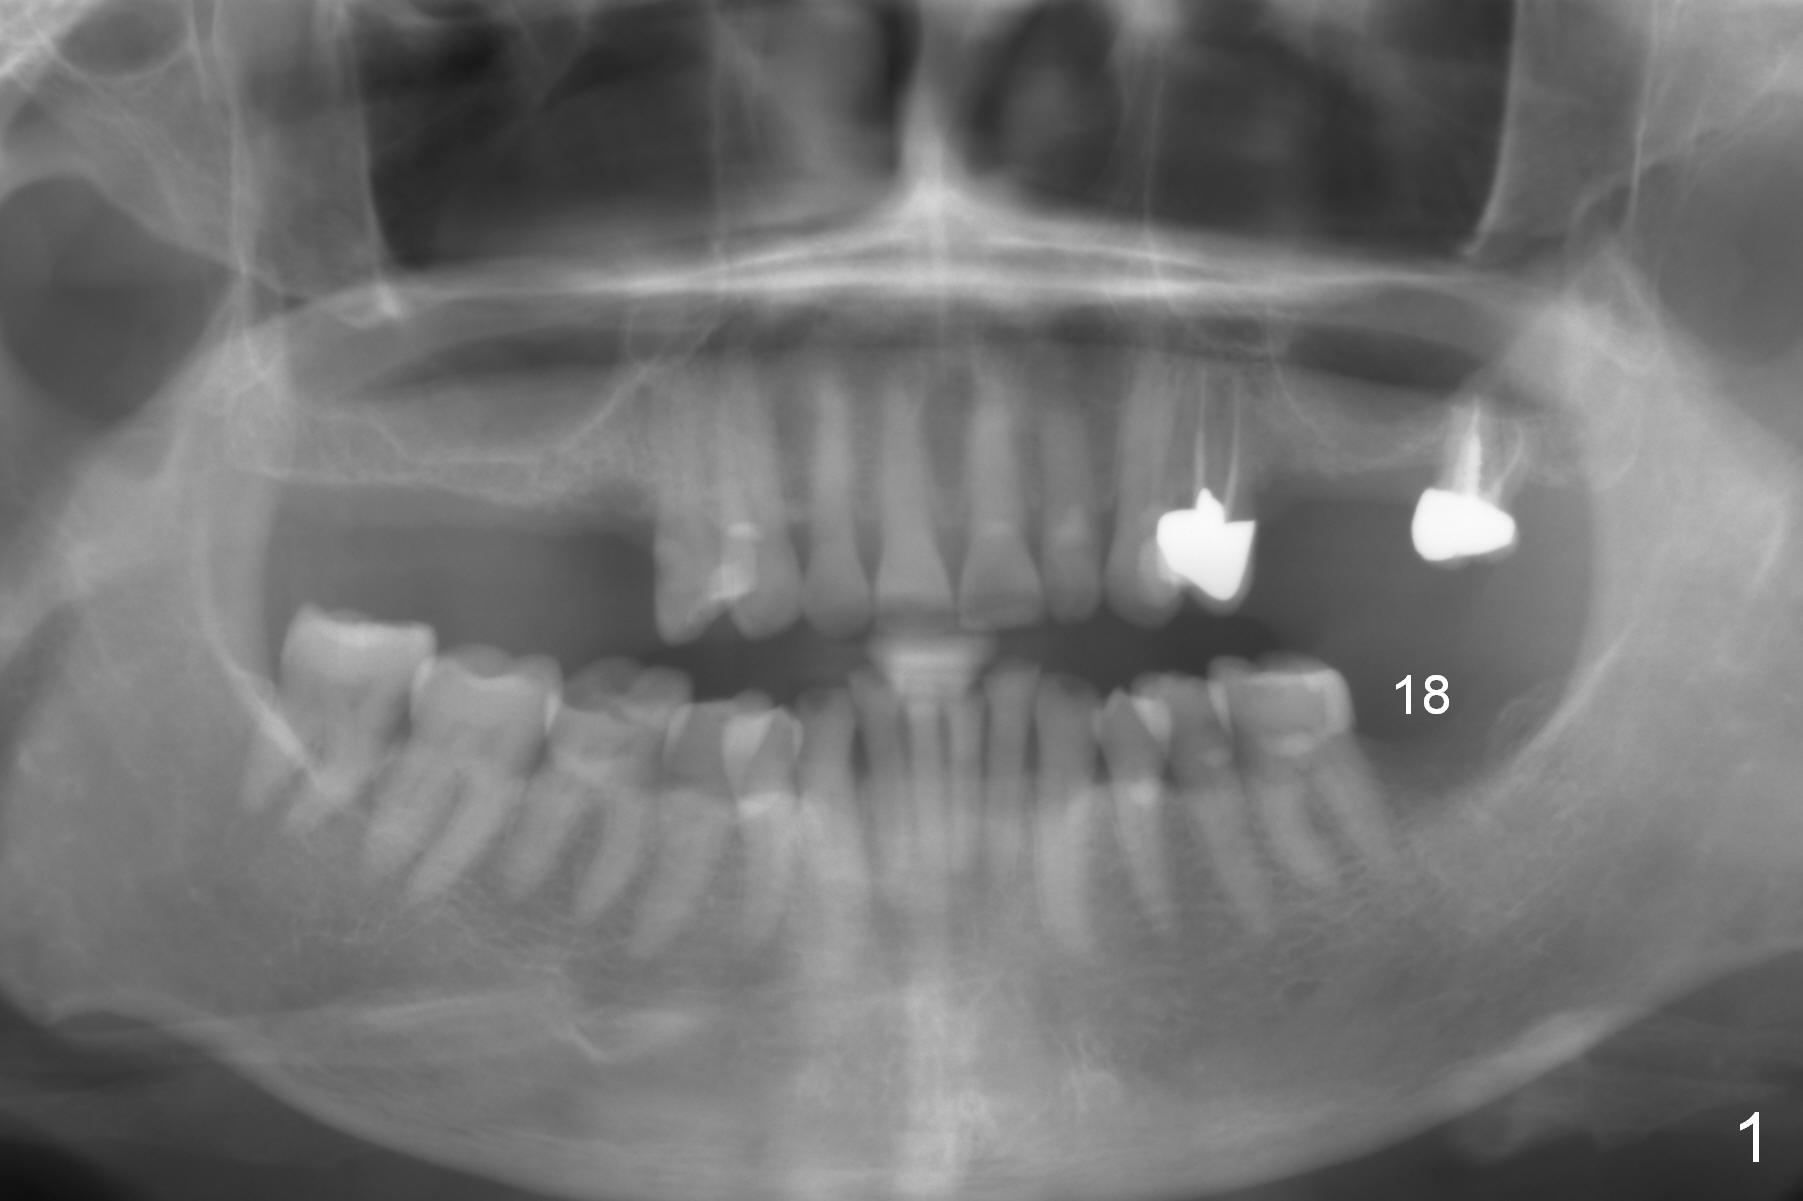

A 65-year-old woman is afraid of dentistry.  After loss of the tooth #18 (Fig.1 with upper RPD), she feels necessary to have an implant (Fig.2).  Since the ridge is wide (Fig.3), a flapless approach is adopted (Magic Split, measure the diameter of its handle).  After 1.6 mm pilot drill (9 mm stopper) and Marking Drill (know the diameter of the large portion), use 4.8 mm Magic Drill (spacer set 2.5 mm, stopper 11 mm).  Try in 5.5x9 mm dummy implant and most likely 6x9 mm definitive one.